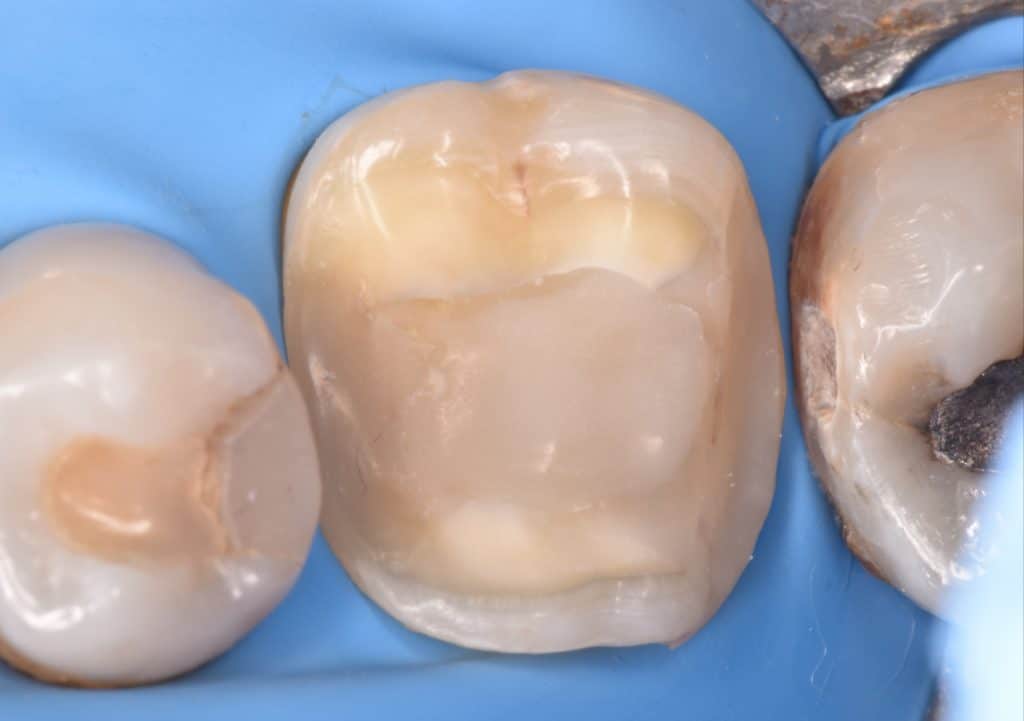

Tooth preparation